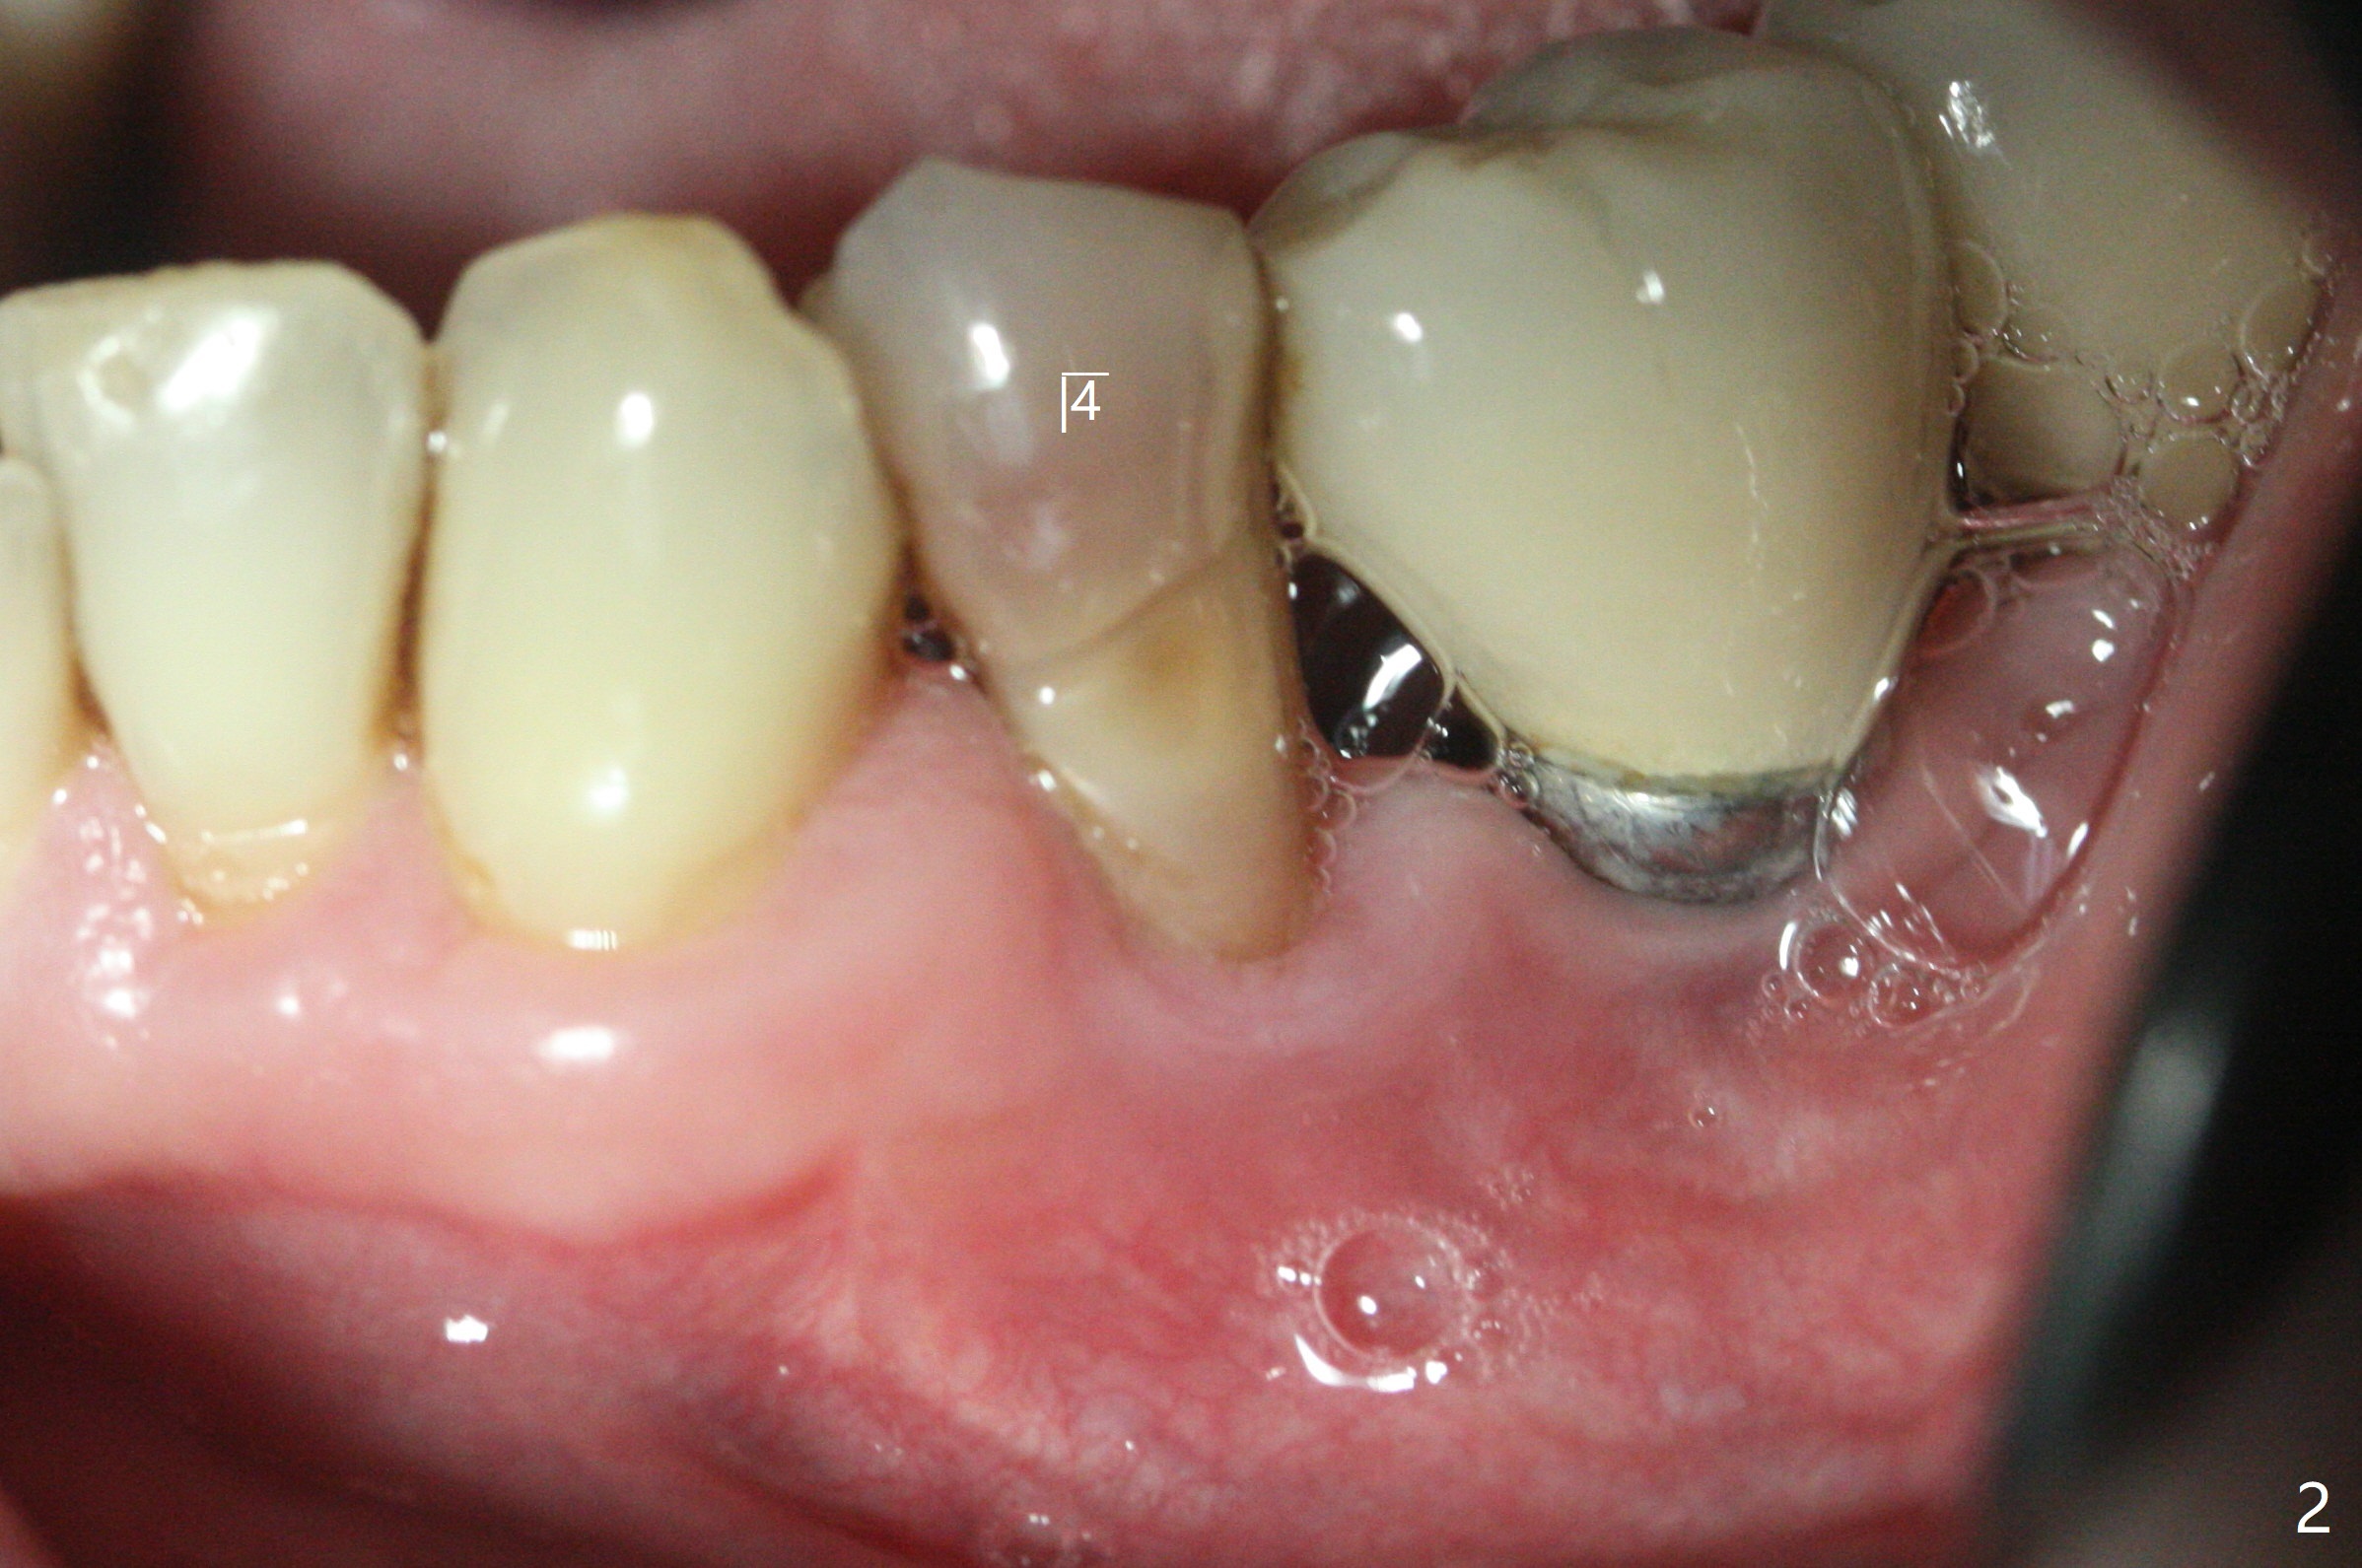

52岁男右下4植体脱落,植骨后,使用左侧咀嚼,发现左下4松动(图一,二),无法吃饭,认为必须拔除植牙(图三,四),徒手种植的邻近植体位置不好,但无骨质吸收(图五,六(牙冠粘固后9年10月)),4种植必须用导板